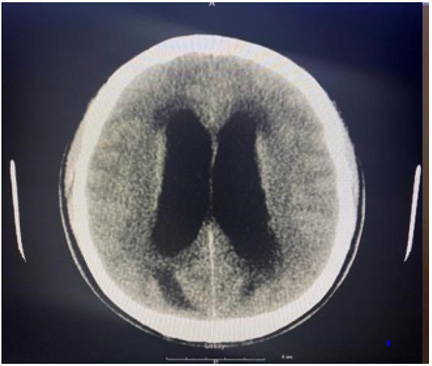

As part of the workup for the patient, a CBC with differential, chemistry panel, CT of the cervical area and ECG were ordered. The CBC test revealed leukocytosis at 13 cells/uL with 80.6% neutrophil and 10.3% lymphocyte relative count. Furthermore, the patient was found to have thrombocytosis at 555x103 cells/uL. The chemistry panel also detected some abnormalities regarding the patient. Calcium and total bilirubin level were elevated at 11.1mg/ dL and 1.7mg/dL respectively. Looking further into the bilirubin count, the patient was found to have an elevated direct bilirubin level of 0.4mg/dL and an elevated indirect bilirubin count of 1.3mg/ dL. Lastly, the patient had a D-Dimer level less than 215ng/mL and a low Creatine Phosphokinase level at 57 U/L. To investigate potential neurological etiologies of the patient’s condition, a noncontrast CT scan was done in three areas of the patient: the brain, face, and cervical spine. The CT scans of the head and cervical spine are indicated by images A and B respectively. Imaging of the brain revealed dilation of lateral ventricles, 3rd ventricle and the cerebral aqueduct. The 4th ventricle, however, was normal in size. The presence of this abnormality definitively indicates the presence of obstructive hydrocephalus. Furthermore, hypoattenuation was detected around the ventricles in the cerebral and cerebellar area. The CT scan found no extra-axial fluid accumulation or depressed skull fractures. Next, facial area imaging found no signs of fractures, temporomandibular joint dislocation, orbital abnormalities, or sinus obstructions. Lastly, while CT imaging of the cervical spine indicated misalignment of the C5 and C6 vertebral bodies, this was likely attributed to motion artifact. In addition, other significant findings include disc narrowing between C7 and T1 and a hypodense appearance of the cervical spinal cord. Other than the abnormal findings, imaging indicated proper cervical spine alignment with no fractures, or prevertebral edema.

In terms of prognosis for the patient, studies show that significant deleterious effects may occur in the long run if hydrocephalus is not treated promptly [5]. Therefore, it is imperative to find the underlying etiology that led to the occurrence of hydrocephalus within the patient. The most probable cause of noncommunicating hydrocephalus within the patient’s age demographic is a ventricular lesion [5]. Nevertheless, no specific tumors were identified on the CT or the MRI making the presence of an obstructive neoplasm unlikely. A potential differential diagnosis can be made for idiopathic cerebral aqueduct stenosis based on the CT imaging indicating dilation of the first three ventricles but not the fourth cerebral ventricle.

Other differentials can also be explored based on the initial imaging of the patient. For instance, the early radiologic finding of ependymal lining enhancement, extensive to the level of T9, is highly suspect of ventriculitis. However, multiple pathologies could explain this event. Although a shunt may be able to explain this finding, leakage of the CSF, as well as meningitis are other possible causes [3]. While the discovery preceded surgical intervention in this patient, ventriculitis may also occur in response to invasive surgical procedures which manage hydrocephalus [4]. Additional analysis of the CT performed on the head, and cervical spine demonstrates changes in neuroanatomy, such as dilated ventricles, resulting from high intracranial pressure. These findings can additionally point towards potential causes of the hydrocephalus. For example, in noncommunicating hydrocephalus caused by spinal cord edema, swelling that extends to at least two vertebral segments above an injured portion is a diagnostic finding [9]. Furthermore, the absence of extra-axial fluid collection is used to rule out potential hydrocephalus ex-vacuo [10].